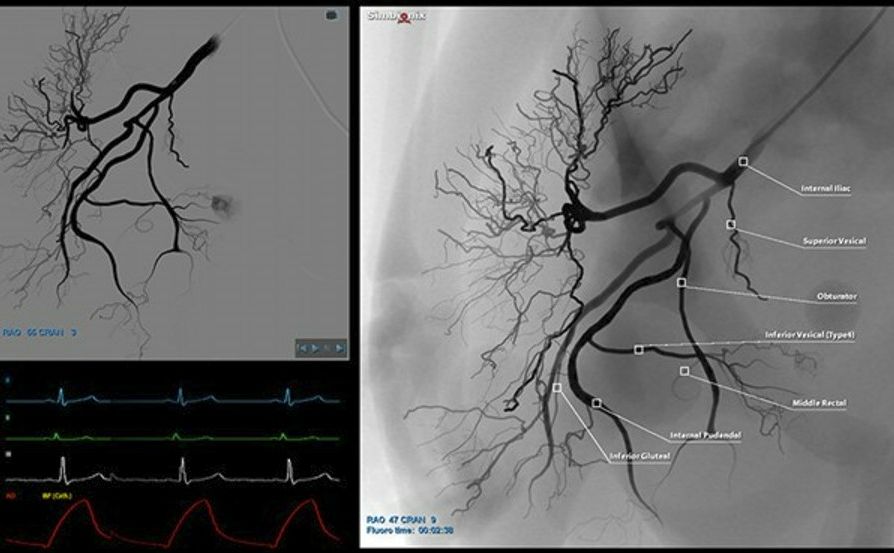

ANGIO PAE.jpg

ANGIO Mentor at SIR

At SIR in booth #758, practice a vast variety of embolization scenarios such as PAE, UFE, HCC using different embolic agents.